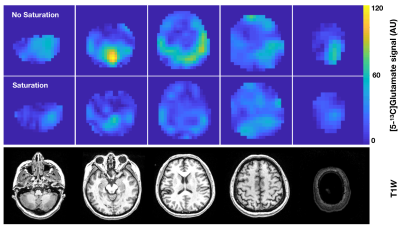

Figure 1 demonstrates the increased level of [5-13C]glutamate with the unsaturated versus saturated lactate flip scheme in the healthy volunteer, with the time-to-injection being 56 s and 53 s, respectively. This translated into an average factor increase in [5-13C]glutamate signal of 2.0. The ratio of [5-13C]glutamate / [2-13C]pyruvate is also shown to be elevated in the unsaturated case. These data collectively demonstrate some level of glutamate and lactate pathway coupling for C2-labeled HP metabolism in the brain, which is suggestive of compartmentalized models hypothesized by prior groups performing saturation experiments with C1-labeled pyruvate.

Figure 1. HP [5-13C]glutamate signal with and without lactate saturation in a healthy volunteer. This translated into an average 2.0-fold increase in [5-13C]glutamate signal without lactate saturation.